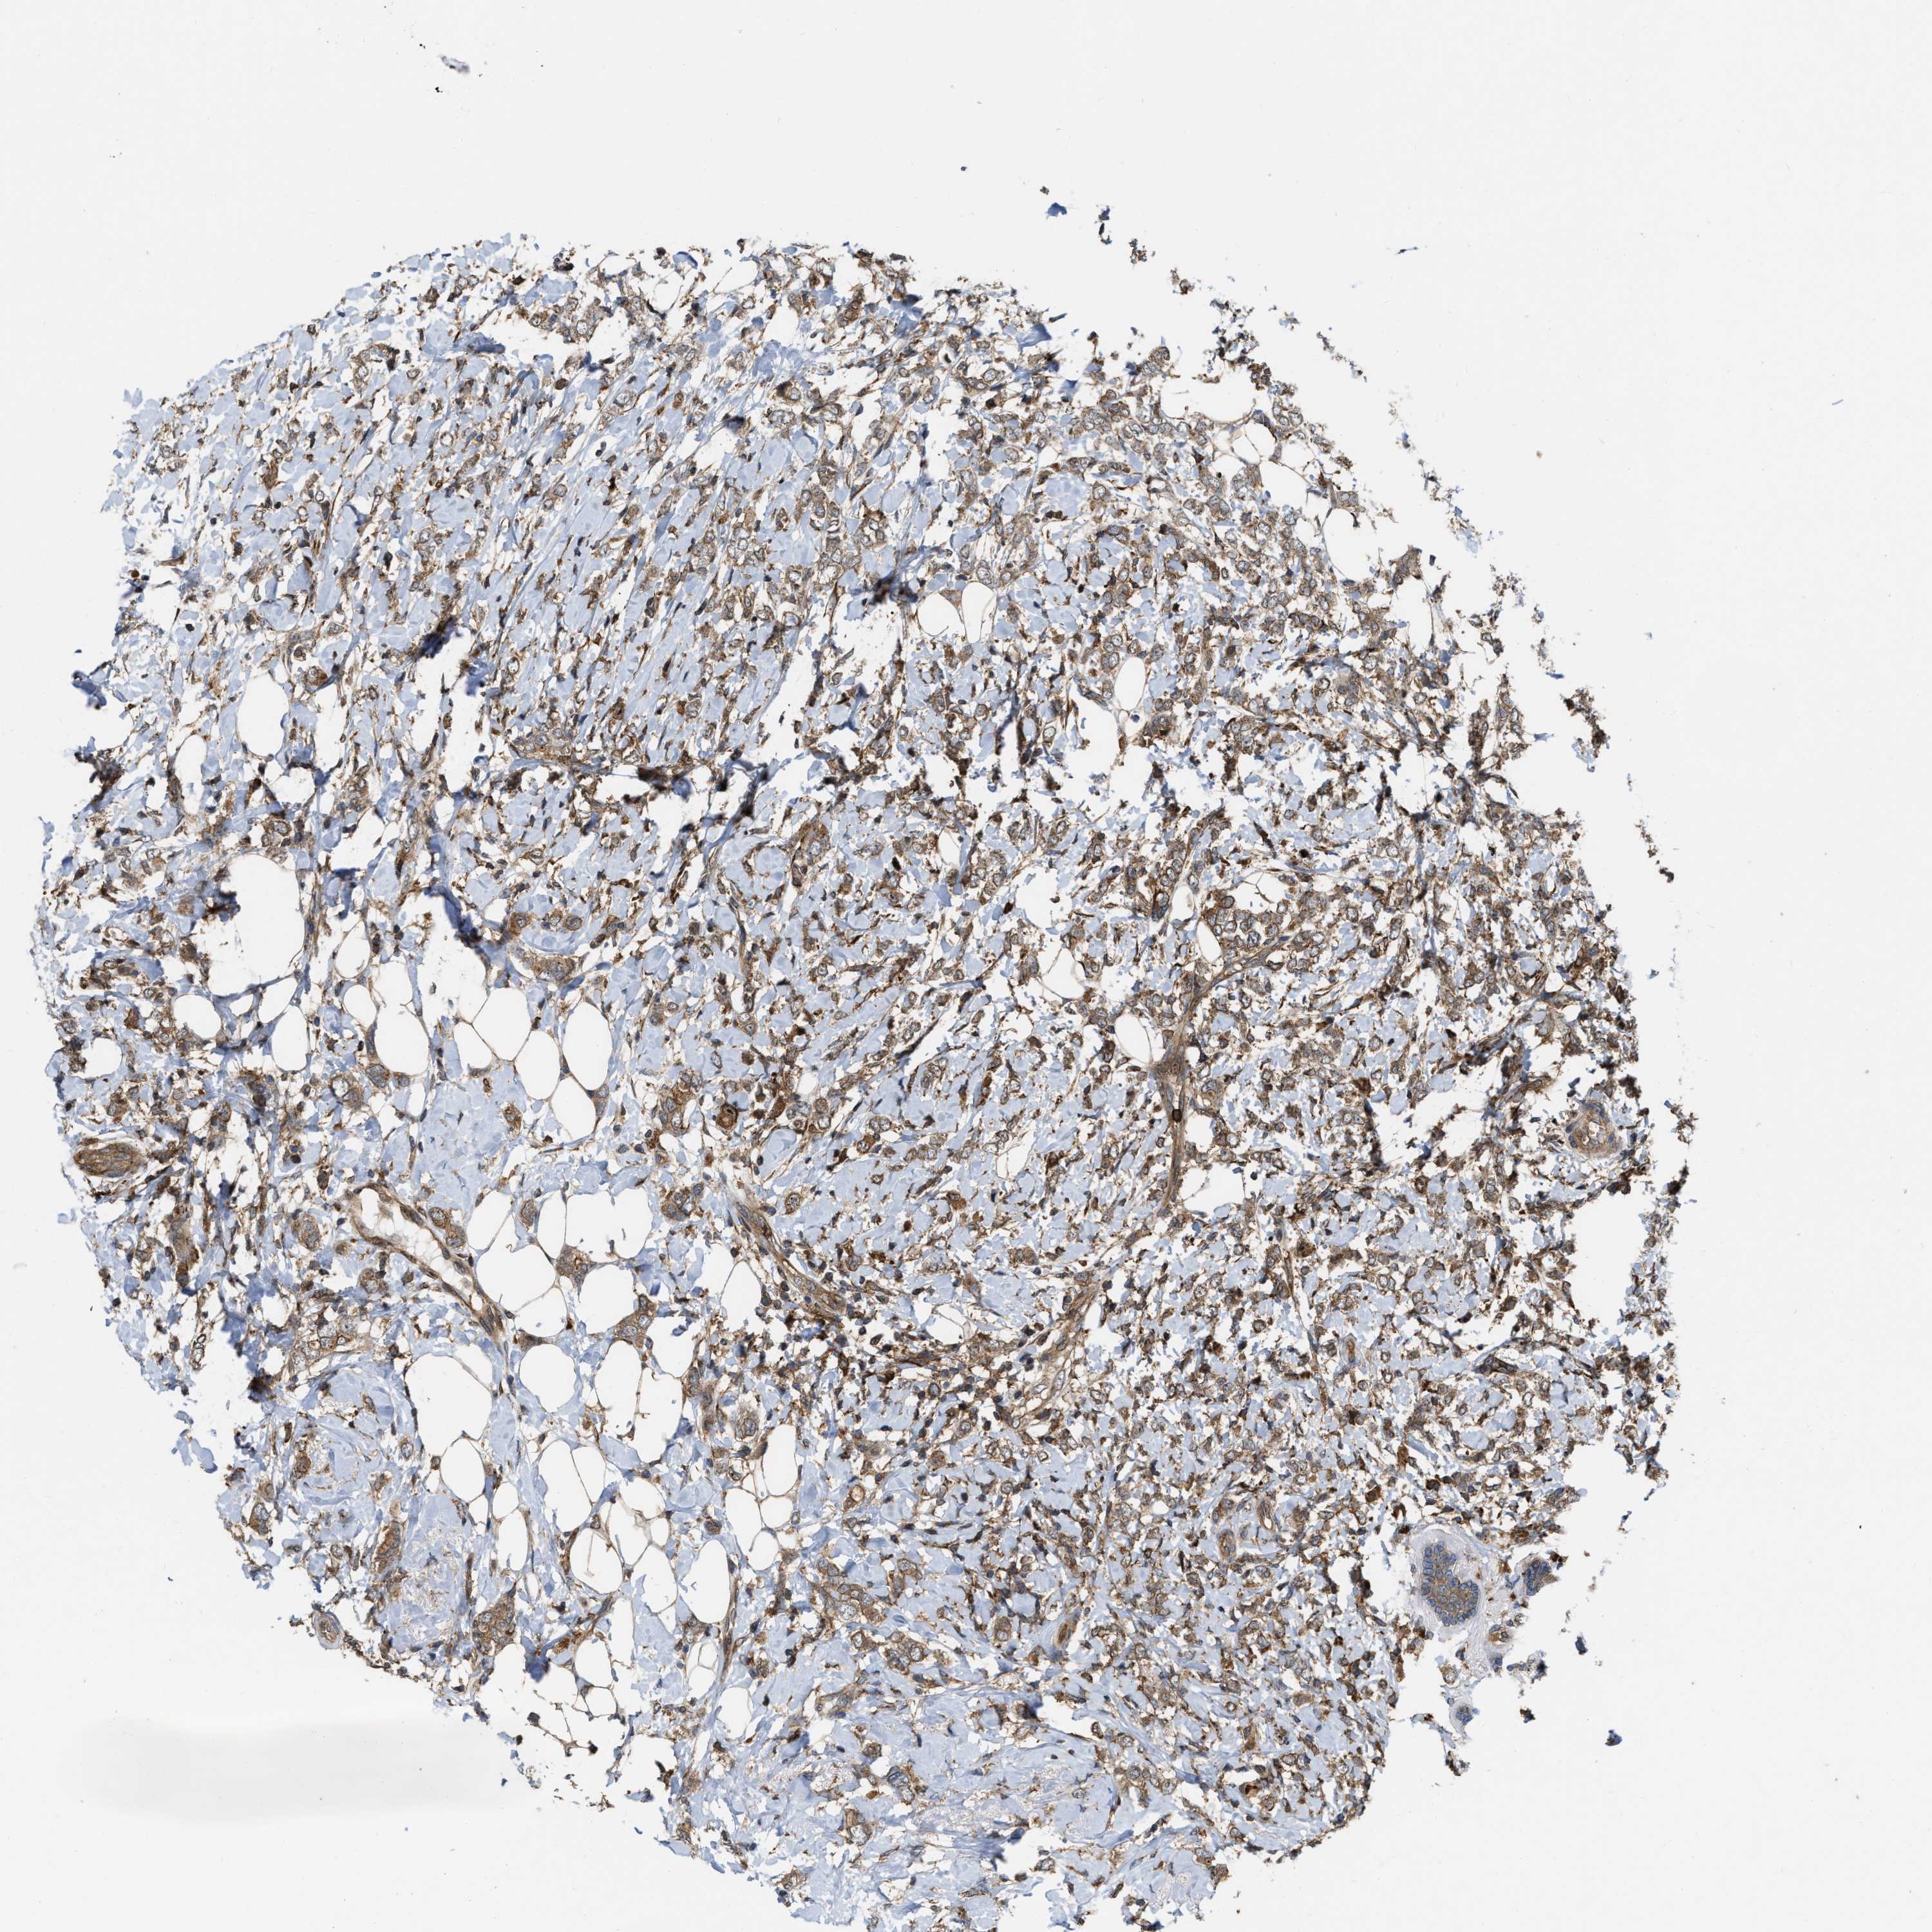

CANCER BREAST CANCER Show tissue menu

BRCA TCGA BRCA VALIDATION PROTEIN EXPRESSION